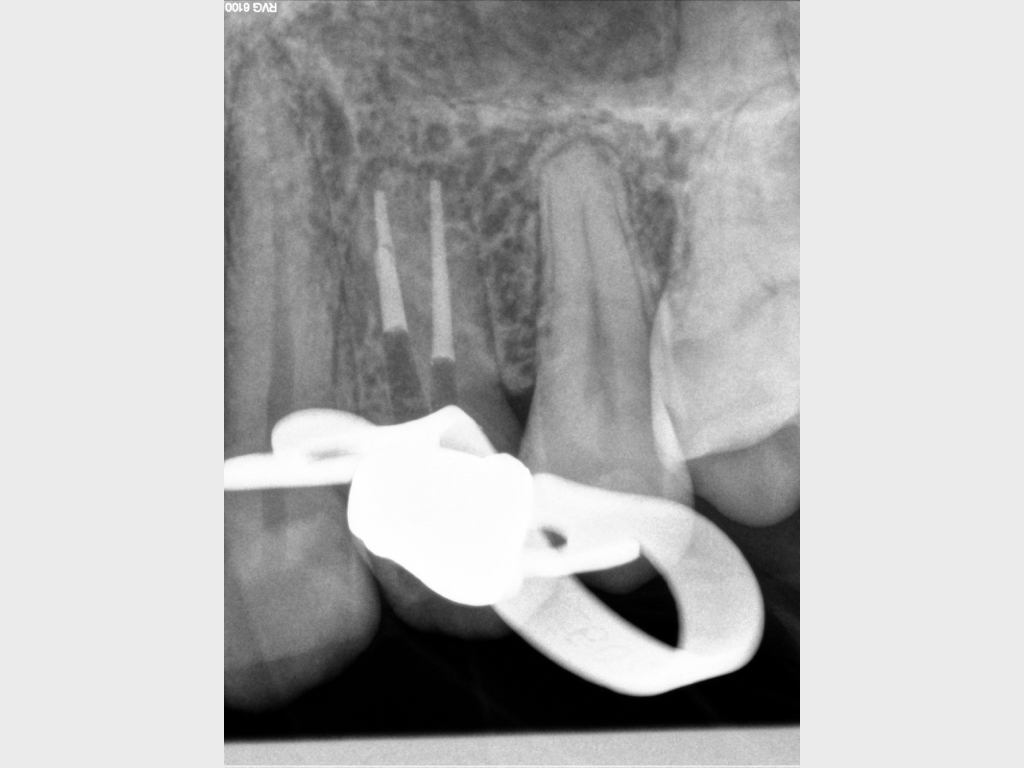

7078.005

Routine